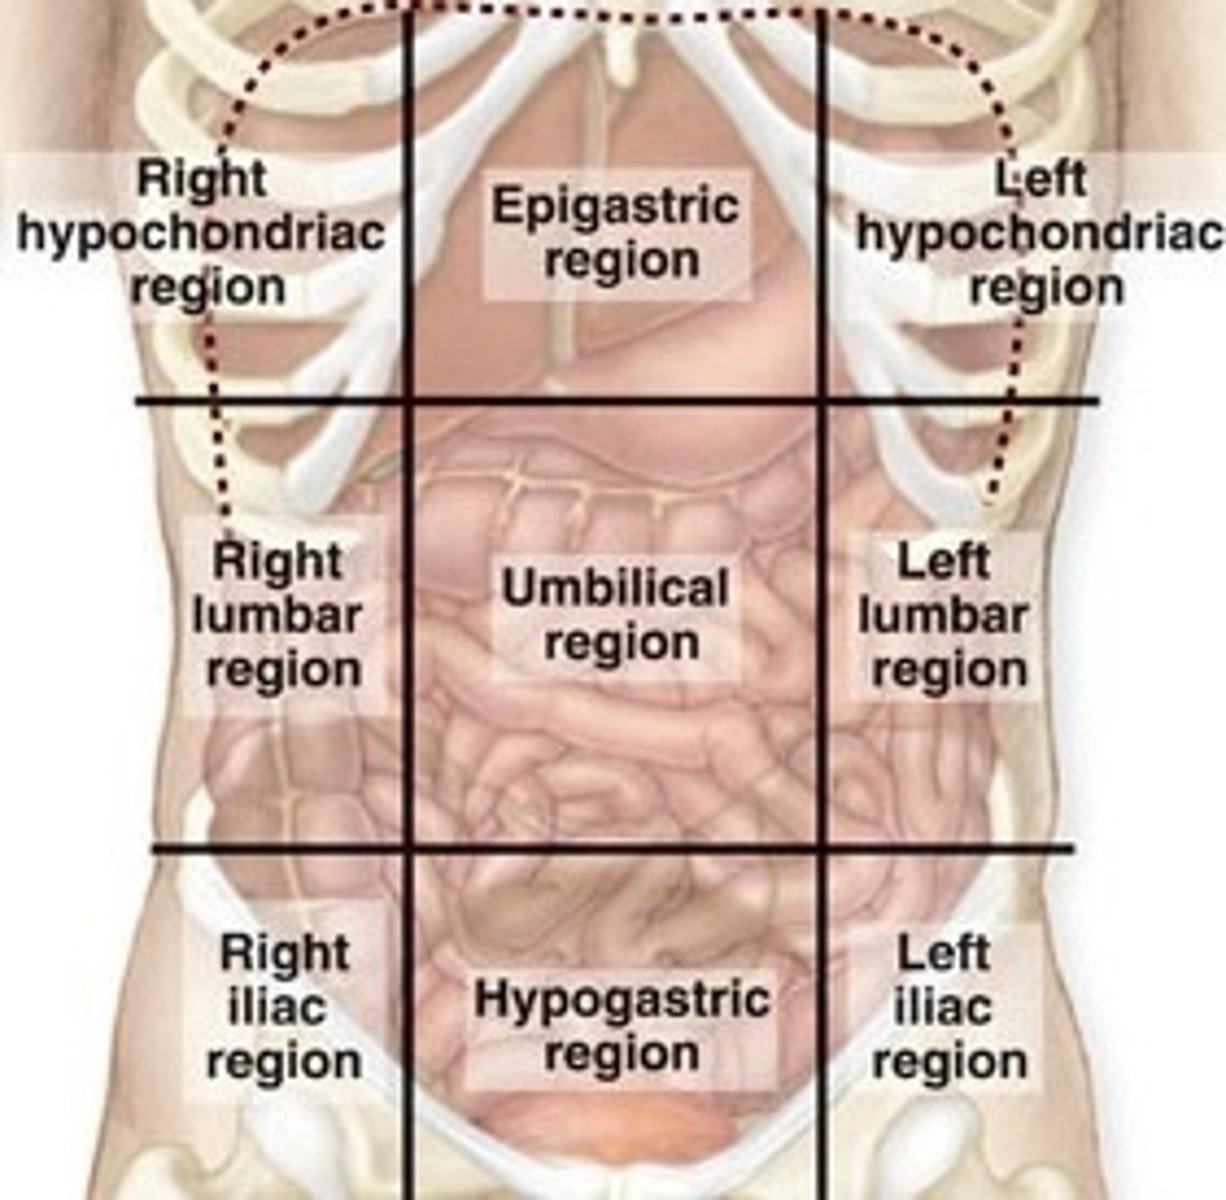

What are all the abdominal regions?

Right Hypochondriac, Epigastric, Left Hypochondriac, Right Lumbar, Umbilical, Left Lumbar, Right Iliac, Hypogastric, Left Iliac

What abdominal region is the liver in?

right hypochondriac